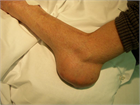

1. 痛風発作既往者や痛風結節を有する者は尿酸降下療法の対象となる(推奨度1)(JG)[1]